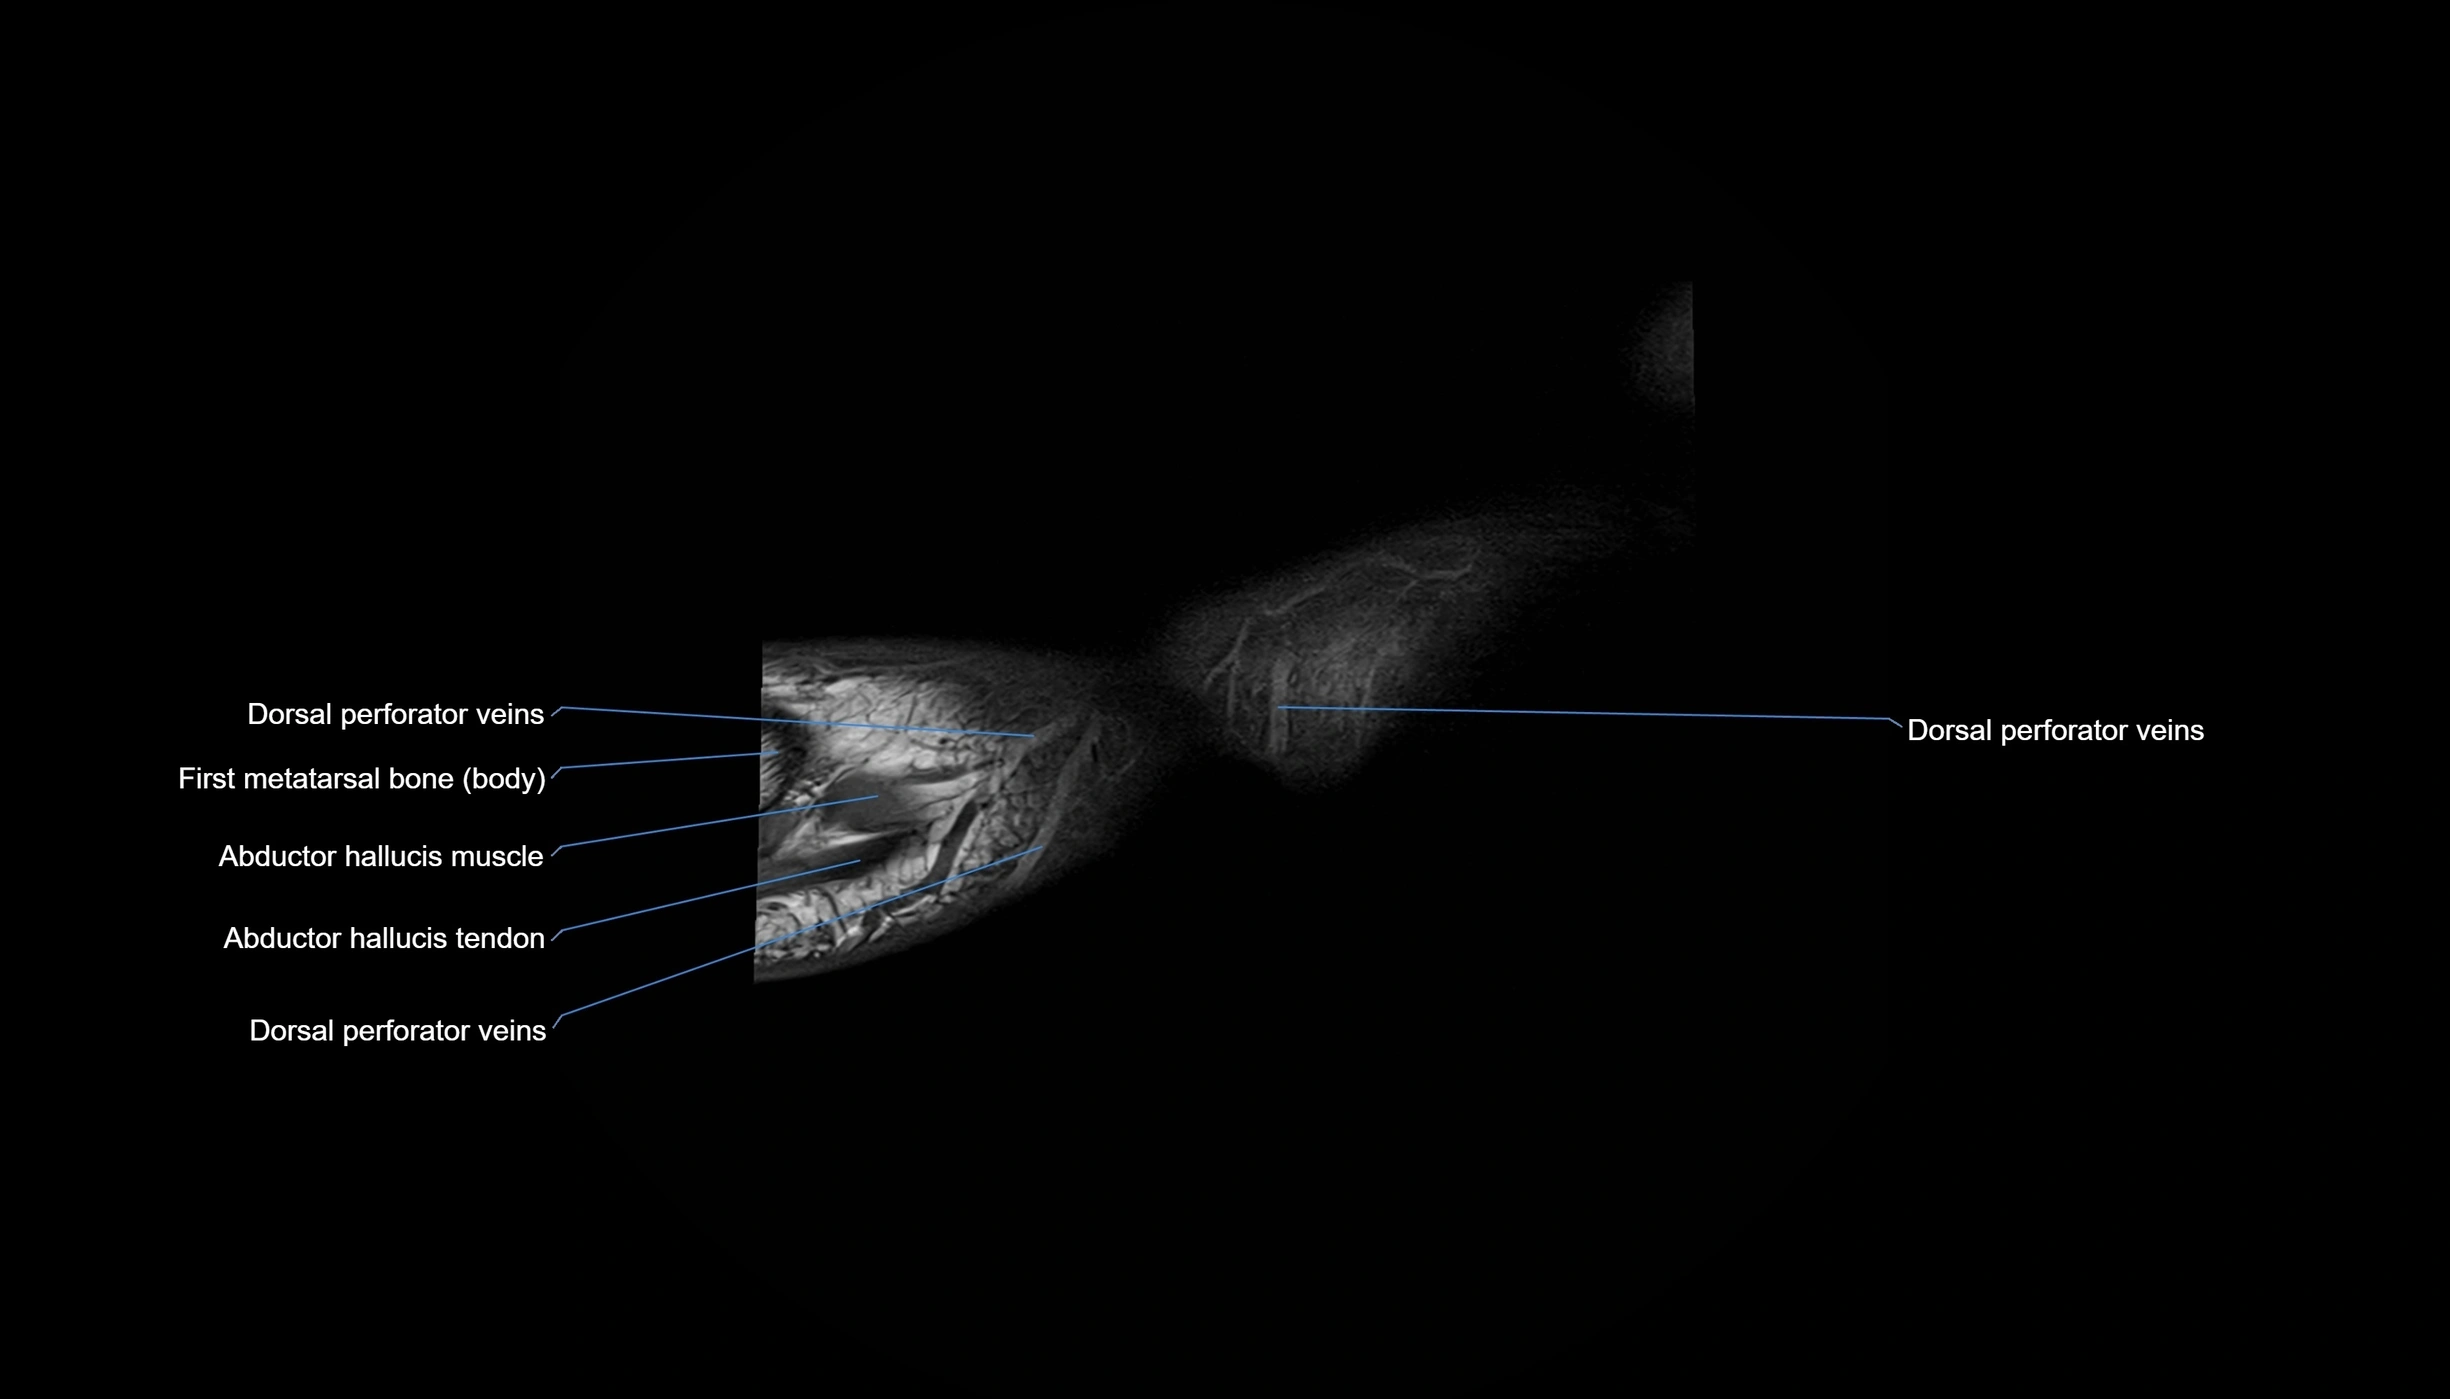

MRI image